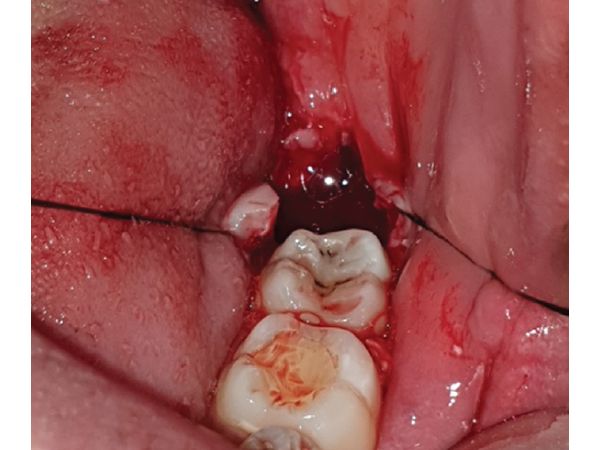

- С помощью хирургического лезвия 15С сделали два разреза на десне таким образом, чтобы получился треугольный лоскут. Этот лоскут отодвинули в сторону, чтобы обнажить кость, покрывающую непрорезавшийся зуб.

- Удалили кость над зубом, сам зуб разрезали хирургическим бором.

- С помощью прямого элеватора, который используется для вывиха и удаления корней, извлекли фрагменты зуба.

- Лунку промыли физиологическим раствором и скорректировали костные неровности. На лунку наложили швы нитью Викрил 6:0.